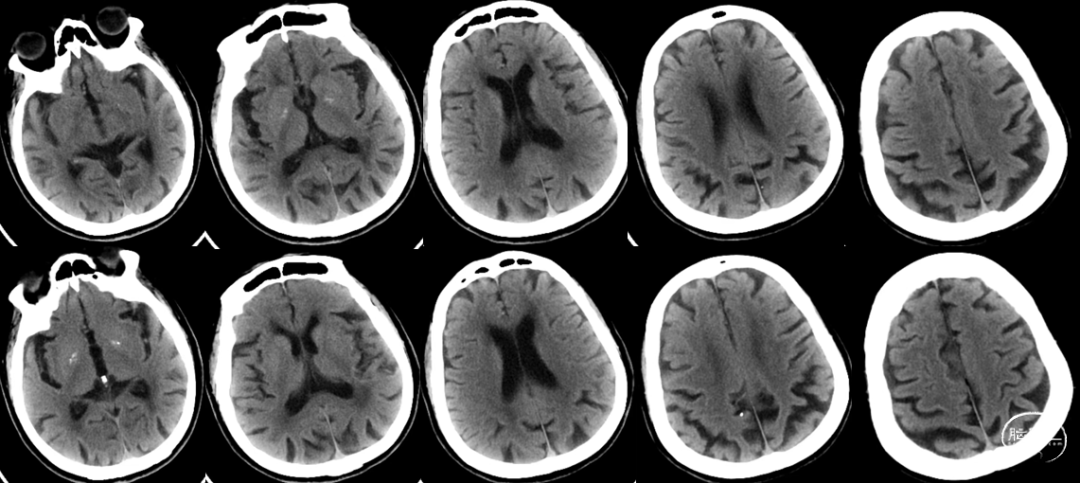

入院时CT:ASPECTS 10分。

术后即刻复查CT,未见出血及造影剂渗出。

查体:神志清楚,言语流利,双侧瞳孔等大正圆,直径约3.0mm,双眼活动正常,无面舌瘫,四肢肢体肌力5级。NIHSS评分0分,mRS评分0分。